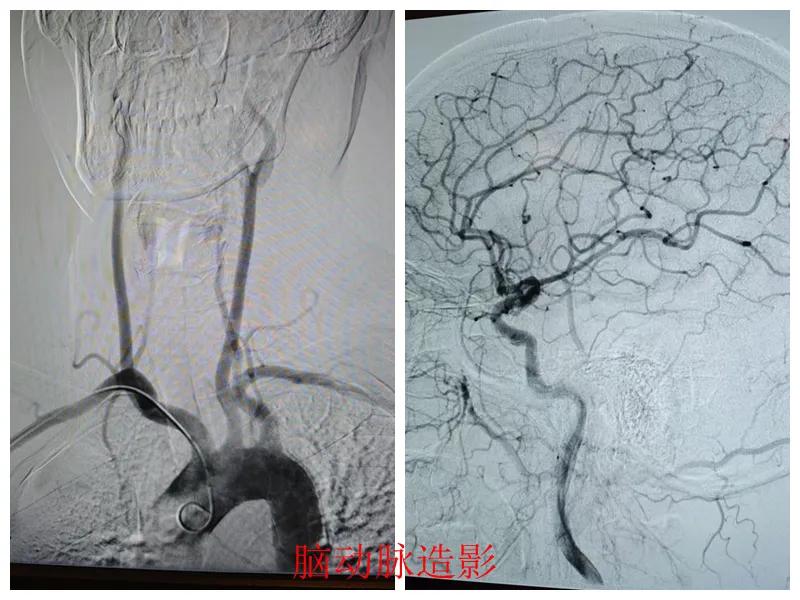

術前準備完善后,在王瑾院長帶領下,心血管內科主任李慧新、影像科主任宋貴良、副主任醫師趙進科等緊密協作,成功為患者實施了冠狀動脈造影及腦動脈造影兩項檢查。冠狀動脈造影結果提示:患者右冠狀動脈慢性閉塞,腦動脈造影提示腦血管多支狹窄病變。